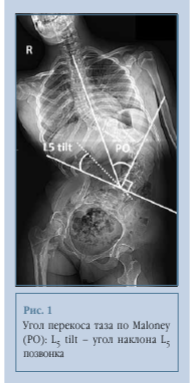

В исследование вошли 45 пациентов 10-17 лет, проходивших лечение в 2012-2024 гг. Всем пациентам выполнены постуральные рентгенограммы (в положении сидя). Величину деформации позвоночника оценивали по методике Cobb до и после операции. Также оценивали параметры сагиттального и фронтального баланса, в том числе во фронтальной плоскости - перекос таза по методике Maloney, наибольшая надежность данного метода показана Shrader et al. [16]. Изучили показатель наклона L5 позвонка, определяемого как угол между линиями, проведенными через верхние границы подвздошных гребней и по краю верхней замыкательной пластинки L5 позвонка (рис. 1).

Возможным объяснением обнаруженной связи может являться то, что пояснично-крестцовое сочленение в норме является очень стабильным благодаря подвздошно-поясничным связкам, фиброзному кольцу и передней продольной связке [18, 20], на основании чего высказано предположение, что стабильное пояснично-крестцовое сочленение может позволить исправить перекос таза за счет коррекции положения L5 позвонка [18, 21]. Это предположение также подтверждается обнаруженной нами прямой связью между коррекцией основной деформации и коррекцией перекоса таза (рис. 1), то есть можно добиться уменьшения перекоса за счет коррекции основной деформации, о чем также сообщали Wild et al. [22] и Frischhut et al. [23]. Исходный наклон L5 позвонка более 15° может говорить о нестабильности пояснично-крестцового сочленения [10, 21], что не позволяет скорректировать положение таза путем изменения положения позвонка, в пользу чего говорит отсутствие достоверной корреляции между наклоном L5 и коррекцией наклона таза в группе III. Возможно, используя тазовую фиксацию, мы можем исправить положение таза в пространстве независимо от исходного наклона L5 позвонка. Выявленные взаимосвязи рентгенологических параметров, влияющие на коррекцию перекоса таза, представлены на рис. 12.

Коррекция перекоса таза не зависит от его исходной величины, что не позволяет в полной мере использовать угол более 15° как показание к тазовой фиксации. Угол наклона L5 позвонка вполне может претендовать на эту роль, так как его высокая исходная величина говорит о нестабильности пояснично-крестцового сегмента, что может не позволить исправить перекос за счет фиксации только до уровня L5, о чем свидетельствует выявленная обратная корреляция между углом наклона L5 и коррекцией перекоса таза в группе без тазовой фиксации.